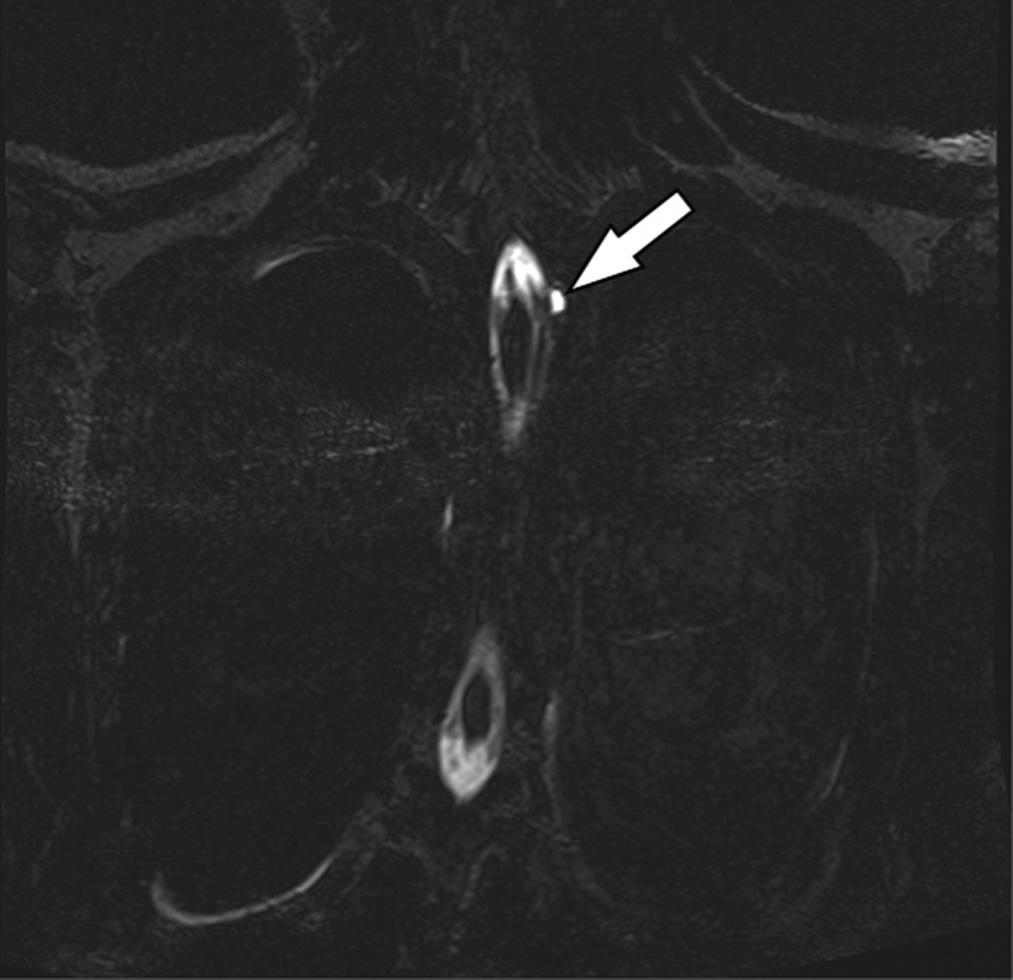

300 Spinal Arachnoid Web

Maiya Smith, Morgan Ketterling, Alexander Gallaer, Rowan Kelner, Christine Raps, Allison M. Beaulieu